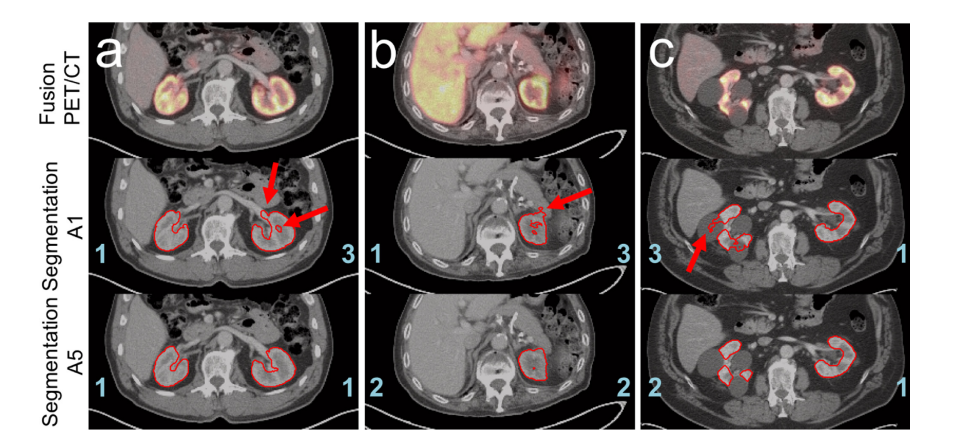

_Figure 7. Examples demonstrating the advantages of a pre-segmentation method. A5. The PET/CT fusion images (top), CT scans showing segmentation contours generated by approach A1 (middle), and those using method A5’s segmentation contours (bottom) were analyzed based on clinical data from three patients. The assigned scores for each segmentation were marked in blue, while any mentioned artifacts are highlighted in red arrows: a: when using approach A1, excessive left renal hilus was segmented, along with a visible hole in the left kidney marrow. In contrast, method A5 avoids these issues entirely. b: both approaches identified missing right kidney tissue; however, approach A1 erroneously included part of the pancreas in its segmentation, whereas this artifact is absent with presegmentation method A5. c: for patients with large renal cysts, approach A1 showed significant difficulties distinguishing between renal tissue and cyst content, leading to substantial misclassification of cystic regions. Method A5 proved far more effective at segmenting kidney tissue while excluding cysts entirely.]

图 7 以展示预分割方法 A5 优势为例